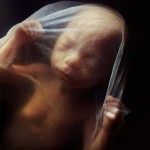

9 to 10-week-old unborn baby – almost half of all abortions happen at this time or later

While early suction abortion may not reveal recognizable body parts, later abortions do. The person witnessing abortion may not see the recognizable parts traveling down the suction tube, but carefully examining the remains as early as 7 weeks post-conception will show arms and legs in the aftermath.